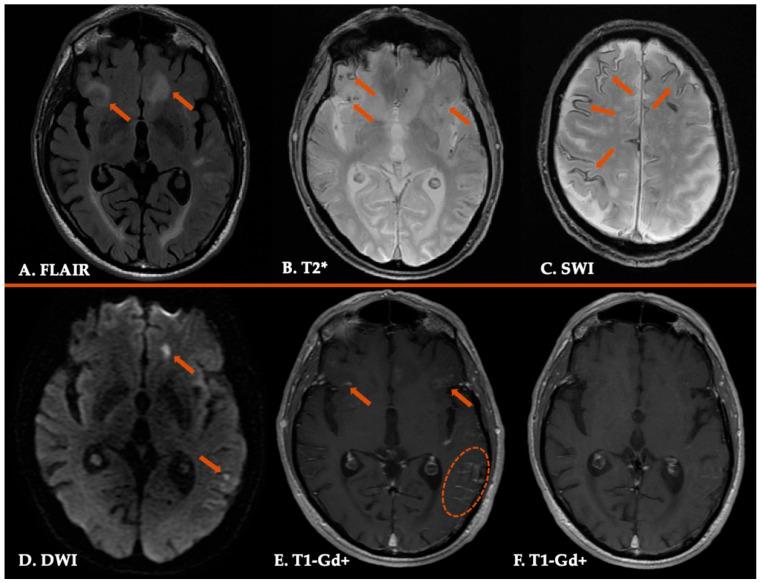

Cerebral amyloid angiopathy (CAA) represents a progressive cerebrovascular disorder, characterized by aberrant accumulation of beta-amyloid isoforms in cortical and leptomeningeal vessel walls of cerebrum and cerebellum. We sought to investigate the clinical manifestations, current different diagnostic tools, various therapeutic strategies and most uncommon subtypes of the disease. The vast majority of CAA remains sporadic, with increasing prevalence with age and very frequent coexistence with Alzheimer's disease. Clinically, CAA can present with spontaneous lobar intracerebral hemorrhage, transient focal neurologic episodes attributed to convexity subarachnoid hemorrhage or cortical superficial siderosis, and progressive cognitive decline leading to dementia. Inflammatory CAA subtype should be recognized early and treated promptly so that better functional outcomes may be achieved. Moreover, genetic and iatrogenic CAA forms are rare, yet increasingly recognized during the last years. Therapeutic management remains challenging for clinicians, especially when markers indicative of higher bleeding risk are present. A targeted therapy does not currently exist. However, various clinical trials are in progress, focusing on offering new promising insights into the disease treatment. This review aims to deepen our understanding of CAA diagnosis and therapeutic approach but also summarizes current evidence on the most uncommon subtypes of this cerebral small-vessel disease.

脑淀粉样血管病(CAA)是一种进行性脑血管疾病,其特征是大脑和小脑皮质及软脑膜血管壁中β淀粉样蛋白亚型异常积聚。我们试图研究该疾病的临床表现、当前不同的诊断工具、各种治疗策略以及最罕见的亚型。绝大多数CAA仍为散发性,患病率随年龄增长而增加,且常与阿尔茨海默病共存。临床上,CAA可表现为自发性脑叶脑出血、因脑凸面蛛网膜下腔出血或皮质表面铁沉积所致的短暂局灶性神经发作,以及导致痴呆的进行性认知衰退。炎症性CAA亚型应尽早识别并及时治疗,以便获得更好的功能预后。此外,遗传性和医源性CAA形式较为罕见,但在过去几年中越来越受到关注。对于临床医生来说,治疗管理仍然具有挑战性,尤其是当存在提示出血风险较高的标志物时。目前尚无靶向治疗方法。然而,各种临床试验正在进行中,旨在为疾病治疗提供新的有前景的见解。这篇综述旨在加深我们对CAA诊断和治疗方法的理解,同时总结关于这种脑小血管疾病最罕见亚型的现有证据。